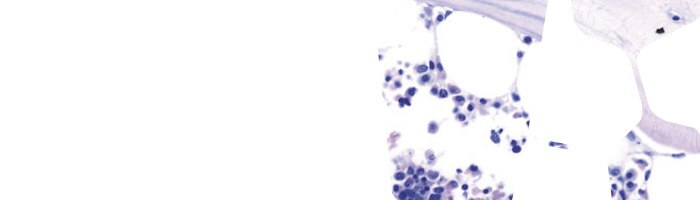

Las disoluciones colorantes de hematoxilina según Gill están diseñadas para ser utilizadas en aplicaciones de histología y citología. Se preparan utilizando hematoxilina en calidad Certistain®. Su formulación perfectamente equilibrada significa que no requieren filtración antes de su uso.

Las disoluciones colorantes de hematoxilina según Gill están diseñadas para ser utilizadas en aplicaciones de histología y citología. Se preparan utilizando hematoxilina en calidad Certistain®. Su formulación perfectamente equilibrada significa que no requieren filtración antes de su uso.